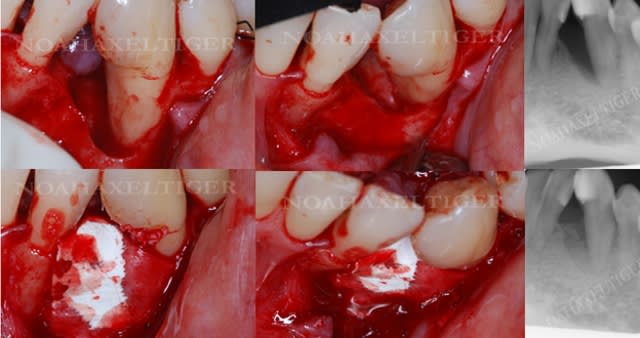

> voila comme promis les 2 cas cliniques.

>

> patiente 1 : paro aggressive, importantes lésions

> angulaires traitées par emdogain sauf mesial 33 où

> j'ai préféré faire une GTR avec comblement

> BioOss.

Superbes résultats !

1 La conservation de la 28 n'est elle pas un facteur défavorable ?

2 la 26 a t'elle été extraite en première intention ou après un échec de la régénération ?

3 avais tu dans ce cas une espèce bactérienne spécifique ?

fracture d'une racine 21, infection vestibulaire

3 et 4 fendu = foutu !

5 oups ... même photo.

6 RTR en place mais extraction du pan vestibulaire seulement pour avoir un site non infecté et une gencive cicatrisée (donc plus facile à suturée)le jour de la pose de l'implant.

lors de l'extraction du morceau vestibulaire, j'ai pu constater que la table externe était partiellement détruite.

si je pose un implant, dois je faire un lambeau pleine épaisseur et mettre une membrane titane (frios) ou plutôt bioguide .

j'ai un peu de mal à savoir comment gérer ce timing.